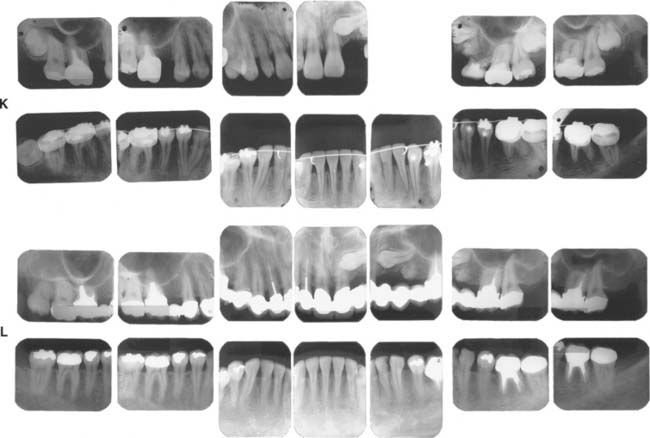

Patients with cast restorations should attend recall visits at least every 6 months. Less frequent recall may lead to oversight of recurrent caries or the development of periodontal disease. Patients who have been provided with extensive fixed prostheses (Fig. 32-6) need more frequent recall appointments, particularly when advanced periodontal disease was present. The appointments can be coordinated by the restorative dentist or the periodontist. To ensure treatment continuity, it is imperative to establish in advance who will assume primary responsibility for coordinating recall appointments.

Fig. 32-6 Patients who have received extensive treatment of this nature require more frequent follow-up care.

Fig. 32-38 Full-mouth rehabilitation with fixed, implant-supported, and removable partial prosthodontics (Treatment VI). Before treatment: Note the reverse smile line and discrepancy in the maxillary central incisor gingival tissue levels. The maxillary first molars had furcation involvement and poor prognosis as a result of periodontal bone loss. A and B, Occlusal views. C, Frontal view. D and E, Right and left views in maximum intercuspation. F, Diagnostic waxing. G, Dental implants were placed to restore the mandibular arch and provide retention and support for a maxillary partial removable dental prosthesis (RDP). H, The gingival tissue levels were corrected with periodontal surgery. I and J, Anterior teeth prepared for fixed restorations. After treatment: K and L, Occlusal views of maxillary arch with and without partial RDP. M, Occlusal view of restored mandibular arch. N and O, Right and left mirror views in maximum intercuspation. P, Frontal view.

Fig. 32-39 Extensive fixed prosthodontics (Treatment VII). Teeth with advanced periodontal disease restored with fixed prosthodontics. A, Initial presentation. The patient required extraction of the right maxillary incisor and surgical correction of the periodontal defects. B, Maxillary teeth prepared for metal-ceramic restorations. C, Reversible hydrocolloid impression. D, Interim restorations. E, Definitive casts. F, Anatomic contour wax patterns. G, Patterns cut back for porcelain application. H, Sprued patterns. I, Metal framework evaluation. J, Opaque porcelain applied. K, Bisque porcelain. L, Centric contacts are on metal. M, Finished restorations before cementation. The extensive prosthesis is segmented with intracoronal rests. N and O, Cemented prostheses.

Fig. 32-40 Extensive fixed and removable prostheses (Treatment VIII). A and B, The patient presented with missing maxillary anterior teeth and mandibular posterior teeth. There was a significant slide from centric relation to maximum intercuspation. The patient was treated with a combination of fixed and removable prostheses. C, Maxillary teeth prepared and foundation restorations placed. D and E, Maxillary teeth waxed to anatomic contour. F and G, Completed fixed restorations. H, Definitive cast for mandibular partial removable dental prosthesis (RDP) framework before duplication. A rotational path of placement was used to engage mesial undercuts in second molars. I, Completed mandibular RDP. Amalgam stops were placed in the first molars to prevent premature wear of the denture teeth. J, Completed treatment. K to O, Appearance 13 years after treatment.

Fig. 32-41 Anticipation of future needs (Treatment IX). A and B, Pretreatment photographs. C to E, Buccal/labial view of bisque bake. F and G, Occlusal view before and at clinical evaluation. Note the location of the occlusal rests to anticipate various future partial removable dental prosthesis designs. An intracoronal rest (dovetail) was incorporated in the left lateral incisor. It is filled with composite resin, which is easily removed if the need arises. H, Completed treatment.

Fig. 32-42 This patient presented with multiple failing restorations and severely compromised function (Treatment X). A to E, Preoperative photographs. F to J, Posttreatment photographs. Where possible, I-bars were used to minimize clasp visibility. Also note the extensive use of metal occlusal surfaces. When prostheses are designed for dentitions with compromised crown/root ratios, precise adjustment of the occlusion and anterior guidance components is critical. K to Q, Seventeen-year follow-up photographs. Note that the maxillary canine was lost and the existing retainer was modified into a pontic through the addition of composite resin. Additional endodontic treatment was needed as time passed. R, Preoperative radiographs. S, Postoperative radiographs. T, Eight-year postoperative radiographs. U, Seventeen-year postoperative radiographs. A fixed dental prosthesis (FDP) was fabricated, replacing the missing tooth #3 with teeth #5, #4, and #2 as abutments. The teeth were prepared with minimal taper, and the castings exhibited good retention. After 10 years, the FDP failed when tooth #2 became dislodged, possibly as a result of the additional loading by the removable dental prosthesis (RDP). Tooth #2 and the pontic were removed, endodontic treatment was performed, a new crown was fabricated, and the #3 pontic was incorporated in a new RDP. Tooth #6 was lost as a result of internal resorption and caries. Initially, the tooth was discolored, but the lesion was inactive, and the attempt to save it failed after 8 years. Its guarded prognosis was discussed as a significant risk factor before treatment initiation. This suggests that teeth with a guarded prognosis can be maintained if attention is paid to the principles of casting adaptation and occlusion.

Fig. 32-43 Long-term follow-up after comprehensive treatment with fixed prostheses of the patient in Fig. 32-41 (Treatment XI). A to E, Preoperative photographs. F to J, Postoperative photographs. K, Preoperative radiographs. L, Fourteen-year postoperative radiographs. If the fixed prostheses have been designed carefully and the patient is cooperative and maintains excellent plaque control, fixed dental prostheses can withstand the test of time. Today, these prostheses continue to provide excellent esthetics and function after more than 16 years of service. Note that no intervention was done for the impacted canine. Initially, this patient presented with only posterior guidance on the left and right first molars. A gingival graft was performed on the left side before the fixed prosthodontic treatment. Fourteen years later, all teeth are stable without any clinically significant mobility, and the anterior guidance components exhibit no visible faceting. No significant change has occurred in bone levels, whereas apparent radiographic bone densities appear slightly increased. Meticulous attention to precise adjustment of the occlusion, especially the anterior guidance component, contributed to the long-term success of this treatment. On the 14-year postoperative radiographs, no signs of occlusal trauma are seen. Also, note that three endodontically treated molars have very large access cavities. Such teeth have a guarded prognosis and are prone to fracture, but no fractures have occurred. Again, this suggests the importance of precise and optimal load distribution at the time of initial treatment and during periodic follow-up appointments. This patient was recalled every 6 months.

Fig. 32-44 Treatment of a severely periodontally compromised dentition (Treatment XII). A to C, Preoperative photographs. D to F, Fourteen-year postoperative photographs. In the initial discussion of an extensive treatment plan with a patient with a severely compromised dentition, the many risks and possibilities of failure must be fully understood by all parties. This extremely complex rehabilitation continues to serve well today. A meticulous design and frequent recall appointments, combined with outstanding home care, enables this patient to enjoy improved function 14 years later. Throughout the follow-up, the patient was seen at 1-month and periodic 3-month recall appointments, depending on pocket charting and patient motivation. Today, tooth #4 has no attached gingiva and little bone support, but no pocket formation. Initially, it was expected that this tooth would be the first to be lost. In conjunction with loss of tooth #1, this would have necessitated a partial removable dental prosthesis or implant-supported fixed dental prosthesis. Occlusal rests, undercuts, and guide planes had been incorporated in the initial prosthesis to anticipate such failure. After more than 14 years, the prostheses continue to serve satisfactorily. The anterior guidance component is starting to show some wear. Throughout the recall, wherever posterior tooth contact was observed in excursive movements, they were eliminated as part of ongoing occlusal adjustment. Meticulous management of load distribution has contributed to the long-term success of this very complex rehabilitation. G, Preoperative radiographs. H, Fourteen-year postoperative radiographs. This patient was referred initially for complete maxillary and mandibular denture fabrication. Before prosthodontic treatment, the periodontal condition was treated. Treatment included a modified Widman flap, performed throughout both arches. A root resection was done for tooth #14, and tooth #30 was hemisected, which resulted in two premolar-like restorations. Use of the severely tilted tooth #17 as a single abutment to support a very long span posed a substantial risk to the long-term success of this treatment, and the tooth’s future loss was anticipated in the design of the prostheses. Another risk was posed by the root structure of tooth #1, with a small, fused root. This tooth was lost after 14 years as a result of a periodontal defect that progressed along a vertical groove in the fused root.

Fig. 32-45 Long-term evaluation (Treatment XIII). A to E, Preoperative photographs. F to J, Eighteen-year posttreatment photographs. Three simple fixed dental prostheses combining conventional and metal-ceramic prostheses with postsoldered connectors continue to serve 18 years after initial placement. Complications over the years included the reshaping of some restorations to correct occlusal discrepancies and the endodontic treatment of tooth #19 through the prosthesis (the access cavity was restored with amalgam). This patient presented with congenitally missing teeth #4 and #12. The maxillary canine was left in the premolar position for use as an abutment with posterior disocclusion resulting from guidance on the canine-shaped pontic. This is not ideal from the perspective of force distribution; however, the canine root successfully withstood the loading over time. Risk factors initially discussed with the patient included uncertainty regarding the effect of the crown/root ratios on the long-term prognosis. At the time of prosthetic treatment, more than 25 years ago, osseous integration was not the reliable treatment modality that it is today. The young woman declined a removable prosthesis as an alternative to fixed dental prostheses. A pinledge retainer was used on the small lateral incisor. Over time, not only was this esthetically effective, but it contributed to long-term maintenance of its periodontal health. Similarly, a pinledge was used on the left mandibular canine, a far more conservative option than a metal-ceramic restoration. If instead metal-ceramic retainers had been used, by now this likely would have resulted in additional treatment needs and possibly the loss of the lateral incisor. Teeth #18, #19, and #3 were treated endodontically; cast posts and cores were used. Also, note that tooth #8 has served well over time. The conservative access cavity was restored, and the favorable position in the arch results in favorable loading. Recall appointments for this patient were scheduled at 6-month intervals throughout the evaluation period. K, Preoperative radiographs. L, Eighteen-year postoperative radiographs.